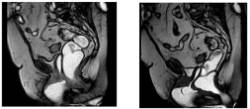

En condiciones normales, el suelo de la pelvis ofrece una resistencia a estos aumentos de presión, de manera que el descenso de los órganos pélvicos como la vejiga y la uretra queda amortiguado por este soporte muscular, manteniéndola cerrada (figura 1, A).

Cuando el soporte muscular de la pelvis está debilitado, el aumento de presión intraabdominal se traduce en un descenso de la uretra que, al no tener una resistencia contra la que cerrarse, permanece abierta desencadenando la pérdida de orina (figura 1, B).

La incontinencia urinaria de urgencia es la que se produce como consecuencia de la urgencia miccional, el deseo brusco e irrefrenable de orinar sin una causa identificable. Esto sucede en ausencia de un llenado vesical completo (figura 2).